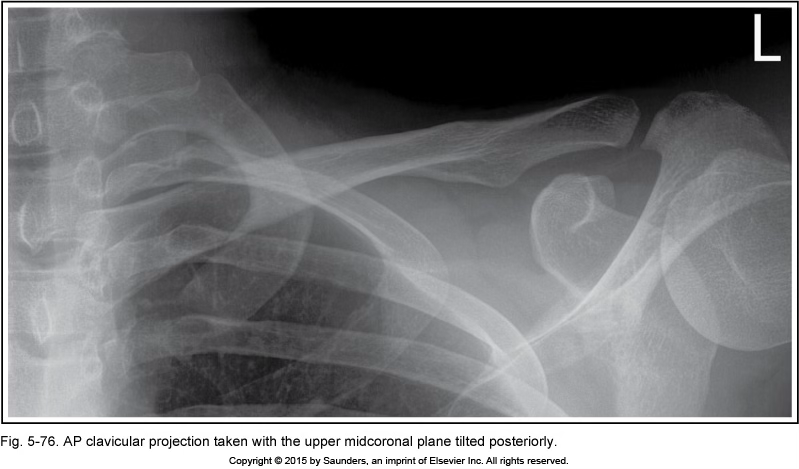

AP clavicle

MCP tilt posteriorly

angle in ribs